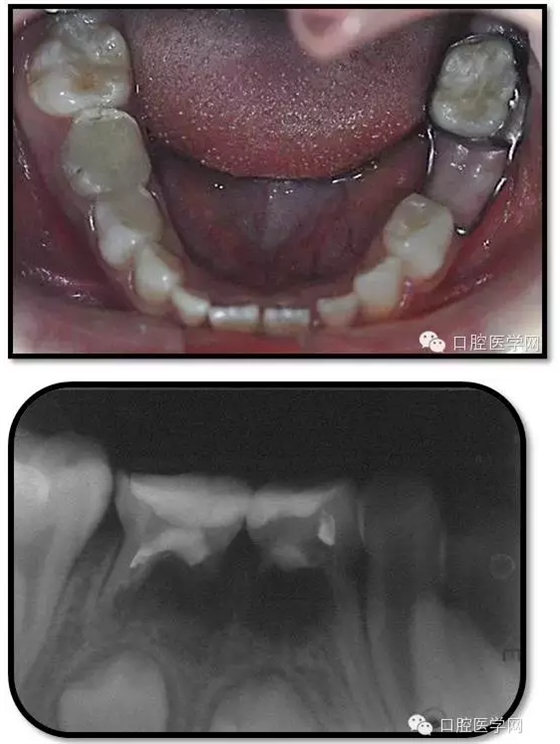

臨床檢查: 75OL齲洞, 舌側(cè)牙體完全劈裂斷端齊齦,探及大量軟化腐質(zhì)。頰側(cè)牙齦紅腫見瘺管,擠壓大量溢膿。叩(±),不松動(dòng)。X線:75根管空虛,牙根吸收約1/2,根尖周及根分歧大面積透射影,35發(fā)育4期,骨硬板尚連續(xù);51殘根,唇側(cè)牙齦瘺管,叩(±),不松動(dòng)。X線:51牙根吸收約1/2,根尖周低密度影。

85O、84DO充填體邊緣不密合,叩(±),不松動(dòng)。84頰側(cè)牙齦略紅腫。X線:84遠(yuǎn)中根及髓室底完全吸收,根分歧透射影,近中根內(nèi)側(cè)見外吸收,44上方骨硬板連續(xù)。85近中根完全吸收,髓室底吸收,根分岐透射影,遠(yuǎn)中根管內(nèi)見根充影像。45發(fā)育4期,骨硬板連續(xù)。

85O、84DO充填完好,邊緣密合,叩(-),不松,齦無紅腫。X線:84、85根分歧透射影,44、45骨硬板連續(xù),恒牙胚上方骨板厚約2-3mm。75帶環(huán)絲圈式間隙保持器完好,無松動(dòng),無咬合不適。64MO中齲。 64MO中齲去腐凈,自酸蝕,SEBOND,樹脂充填。 口腔衛(wèi)生宣教,囑3個(gè)月后復(fù)診。

1、根分歧處病變姑息保留牙的治療及轉(zhuǎn)歸。 75牙體缺損過大,根分岐大面積透射影并累及根尖周。故拔除后間隙保持。84、85初診時(shí)已做過根管治療,有繼發(fā)齲,牙根吸收較多,可見大面積的根分歧病變,但根尖無病變,考慮44、45表面骨硬板連續(xù),故只對(duì)患牙進(jìn)行了繼發(fā)齲充填治療,姑息保留。3個(gè)月復(fù)查時(shí),85O、84DO充填完好,邊緣密合,叩(-),不松,齦無紅腫。7個(gè)月復(fù)查時(shí)85O、84DO充填完好,邊緣密合,叩(-),不松,齦無紅腫。X線:84、85根分歧透射影,44、45骨硬板連續(xù)。 回顧整個(gè)治療過程,應(yīng)定期復(fù)查84、85姑息保留牙,且間隔時(shí)間不宜過長(zhǎng)。觀察根分歧病變的恢復(fù)情況,一旦發(fā)現(xiàn)恒牙胚受累及,則需采取積極措施。